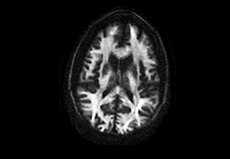

• Conjunto de bobinas e bobina para cabeça com 48 canais

A bobina para cabeça opcional com 48 canais oferece um desempenho fenomenal para todos os pacientes. Seu design ajustável atende a 99,99% da população de pacientes, ao mesmo tempo em que preserva a alta SNR. Ela também maximiza os recursos clínicos de aplicações avançadas de imagiologia, como as tecnologias HyperWorks, e é compatível com EEG (eletroencefalograma) e fMRI, simultaneamente.

atende a

99,99%

da população de pacientes.